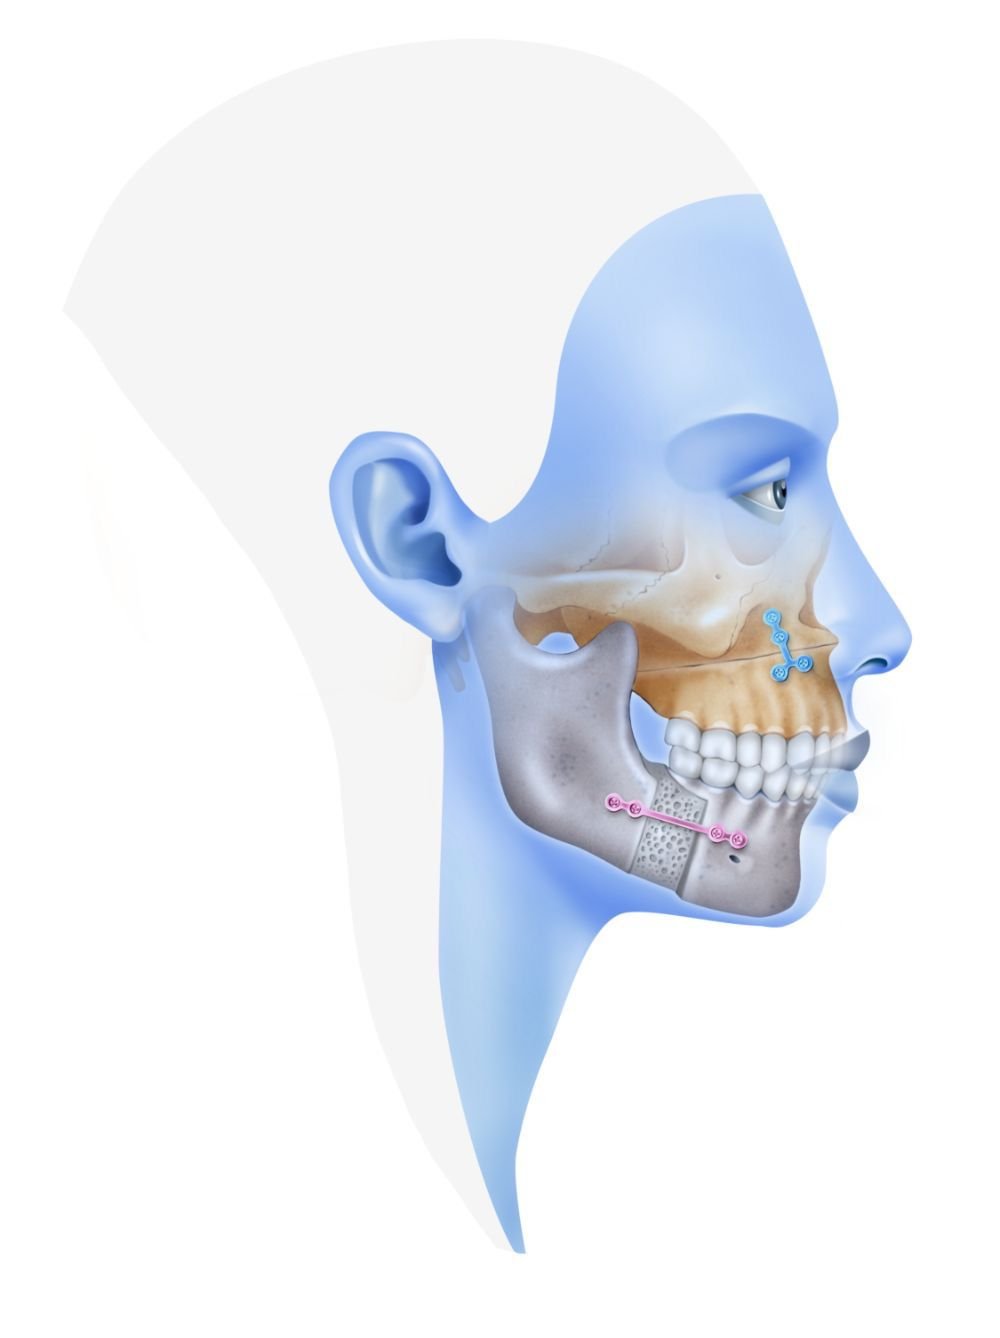

Oral & Maxillofacial Surgery is a specialized field that focuses on diagnosis and surgical treatment of complex conditions involving the mouth, jaws, face, and surrounding structures.

Oral & Maxillofacial Surgery is a dental specialty that addresses complex surgical procedures related to:

▪ Jawbone Surgery & Preparation

▪ Pre-Implant & Advanced Implant Surgery

🖥️ Digital Diagnosis & Surgical Planning

🦷 Oral Surgery & Implant Dentistry